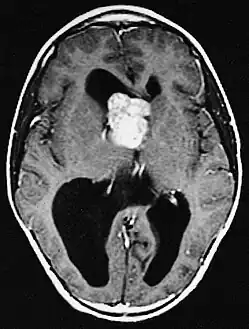

a,b)Images of subependymal giant cell astrocytomas arrowheads -

MRI of brain with sub-ependymal giant cell astrocytoma

Diagnosis is made by imaging with a contrast-enhanced MRI or CT scan of the brain.[3]